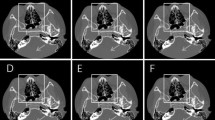

Table 1 presents the results of the qualitative image analyses. Figures 2, 3, 4, and 5 contain representative CT images. The scores assigned by both readers to the depictions of the otic capsule, auditory ossicles, and tympanic membrane were statistically significantly improved for the DLR images compared with the HIR images (p ≤ 0.003). One reader scored the depictions of the osseous spiral lamina and cochlear axis as significantly superior for the DLR images compared with the HIR images (p < 0.001). Qualitative image noise was rated to be significantly reduced in the DLR images compared with the HIR images (both readers, p < 0.001). In addition, both readers rated the overall image quality as significantly improved in the DLR images compared with the HIR images (p < 0.001).

Computed tomography (CT) images of a 73-year-old female patient after a deep learning reconstruction (DLR) and b hybrid iterative reconstruction (HIR). The depiction of the auditory ossicles (arrow) was rated as 5/3 and 4/3 (DLR/HIR), and the depiction of the tympanic membrane was rated as 5/3 and 3/3 (DLR/HIR) by readers 1 and 2, respectively

Computed tomography (CT) images of a 58-year-old male patient after a deep learning reconstruction (DLR) and b hybrid iterative reconstruction (HIR). Perforation of the tympanic membrane (arrow) is more clearly depicted in a. The depiction of the tympanic membrane was rated as 5/3 and 4/3 (DLR/HIR) by readers 1 and 2, respectively